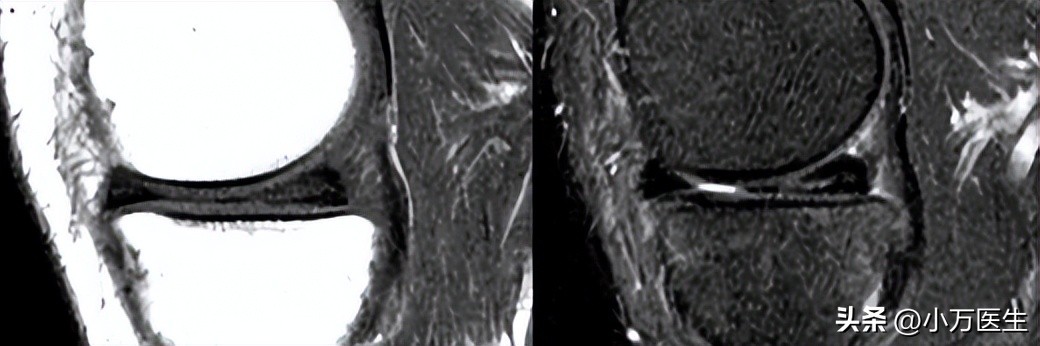

可以有效诊断半月板损伤,诊断准确率为90%。0-Ⅲ级法:Reicher MA和Lotysch于1986年首先提出。关节磁共振检查除了能发现半月板损伤外,同时还能发现关节内韧带、软骨以及关节外的病损,能有效减少漏诊机会。

0级:为正常的半月板,呈均匀的低信号,半月板形态规则。

(0级)

Ⅰ级:表现为不与半月板关节面相接触的灶性的椭圆形或球状的信号增高影。

(Ⅰ级)

Ⅱ级:表现为线性的半月板内信号增高,可延伸至半月板的关节囊缘,但未达到半月板的关节面缘-半月板内撕裂。

(Ⅱ级)

Ⅲ级:半月板内的高信号达到半月板的关节面,半月板的撕裂。

(Ⅲ级)